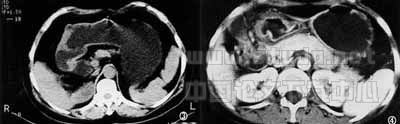

图4 胃窦部胃癌Ⅲ期,胃窦部肿块与胰腺粘连,胰胃脂肪间隙消失。

图5 与图4同一患者侧位像示胃窦部肿块仍与胰腺粘连,手术证实肿瘤广泛外侵,未能切除。

图6 胃底部胃癌Ⅳ期,胃底部肿块突破浆膜,胃壁外缘毛糙,肝内出现小结节状转移灶。

3.2 胃癌的CT表现及其鉴别诊断 (1)胃壁异常增厚,胃壁线僵硬:根据40例正常成人胃壁厚度的测量结果,结合国内外,我们认为胃食管交界处胃壁厚度>8mm、其余部分胃壁厚度>5mm视为异常增厚。胃壁异常增厚,胃壁线僵硬是病变自粘膜面向深层浸润的结果,当病变侵及浆膜层时,胃壁外缘毛糙,出现结节样改变,见图6。(2)腔内外肿块:肿瘤向腔内外生长时,CT可清楚地于扩张的胃腔内外显示形态不规则的软组织肿块,伴有病变附着处胃壁增厚。团注增强扫描肿块呈均匀性或不均匀性强化。(3)肿瘤向周围浸润:胃癌突破浆膜浸润胃周,CT表现为胃周脂肪层模糊,密度增高,并显示有不规则条带状高密度影。肿瘤直接侵犯邻近脏器,以胰腺最易受侵,CT表现为脏器间脂肪间隙完全消失,肿块与受侵脏器紧密相接,见图5。但有时与肿瘤非癌性粘连较难鉴别。国外文献报道胃癌侵犯胰腺的假阳性率高达12%~30%[1,2]。我们采用薄层扫描及改变体位扫描有利于鉴别,但其假阳性率仍有10%。(4)淋巴结转移:胃服水后有利于胃周围肿大淋巴结的显示,薄层螺旋CT扫描更有助于发现和判断淋巴结的大小。本组资料显示CT发现肿大淋巴结的敏感性为88.5%,特异性为92.3%,对胃周<0.5cm的淋巴结CT发现率仍较低,为38%,较文献报道的23%[2,3]稍高。